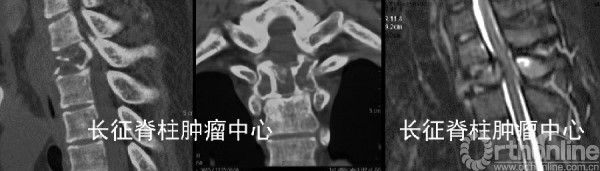

第一次术前CT、MRI均提示胸2椎体溶骨性破坏。

当地医院行后路胸2椎体次全切除取髂骨植骨重建内固定术,术后5月,X线,CT及MRI均提示胸1-3椎体溶骨性破坏,考虑胸2肿瘤组织残留、复发并侵及邻近椎节。